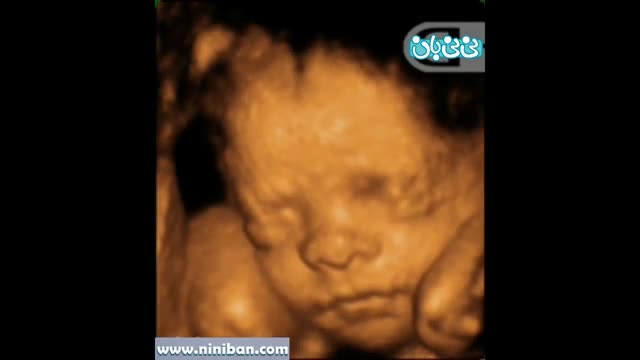

سونوگرافی چهار بعدی در بارداری هفته بیست و نهم